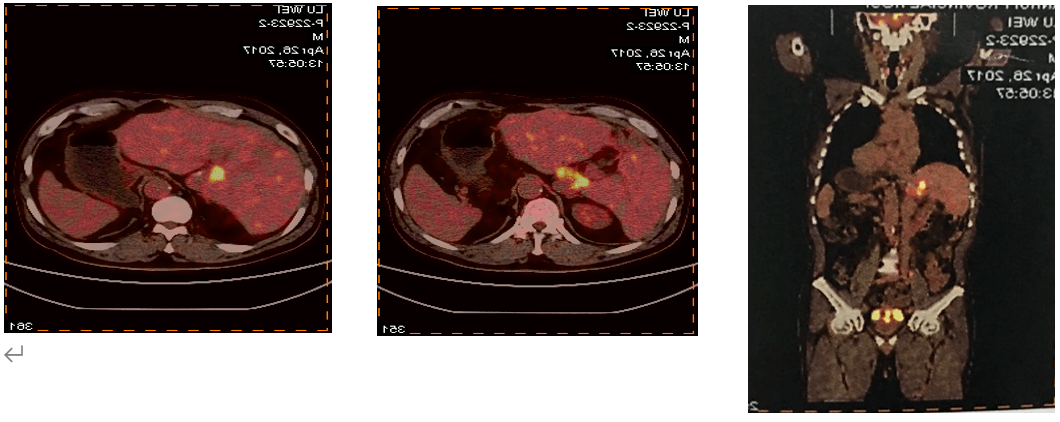

肾脏淋巴瘤PETCT检查案例

554x471 - 451KB - PNG